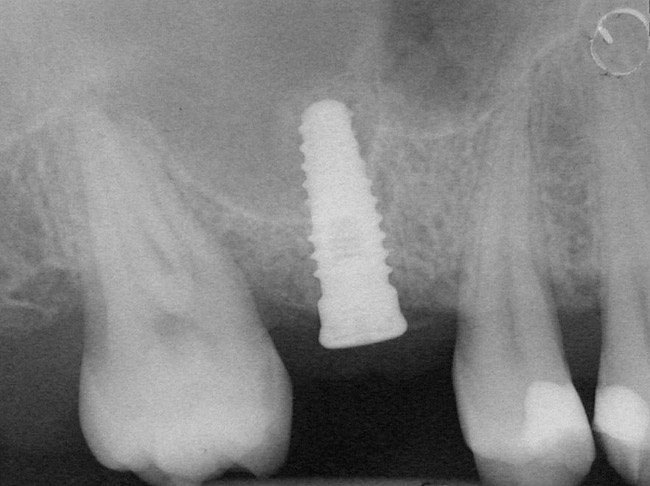

A full-thickness mucoperiosteal flap was raised, and alternating osteotomes were used to prepare the implant site. After achieving a length of 7 mm (Figure 7A and Figure 7B), heterologous bone graft was implanted and the osteotome sequence was repeated. The implant showed primary stability.

Figure 8  At 4 months after treatment, the radiograph revealed the presence of a bone layer surrounding the implant.

Figure 8